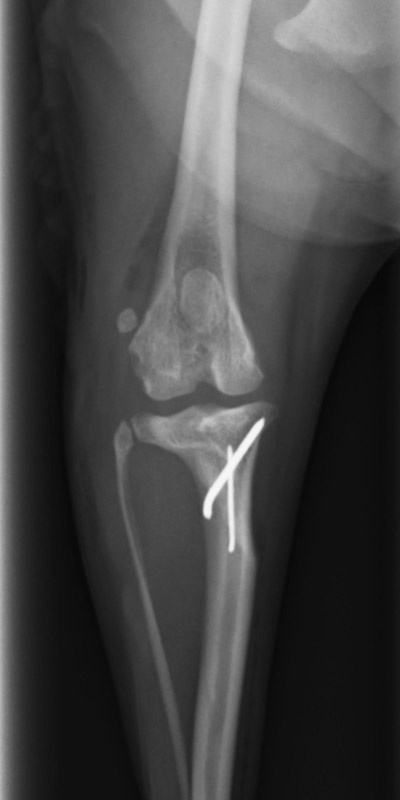

前十字靱帯断裂

柴犬(10歳)

持続する右後肢の挙上、疼痛

手術前

手術後